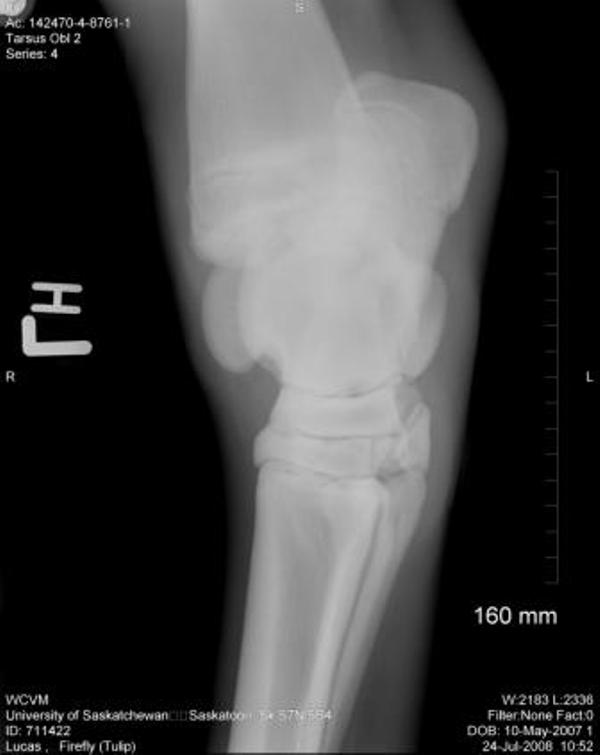

As there were some left hock abnormalities noted, I am now posting her hock pictures.

Bilateral Tarsi:

Left Tarsus:

There is a small osseous protrusion off of the distal aspect of the medial trochlear ridge. This is a normal variation. There is also a very small linear osseous fragment visible dorsal to the proximal intertarsal joint in the lateral view This may be a normal finding or it may be a small osseous fragment from more proximity in the tarsus. No Obvious defect or origin of this fragment is noted, however.